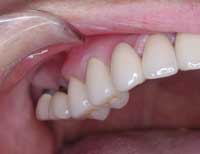

| Before | After |